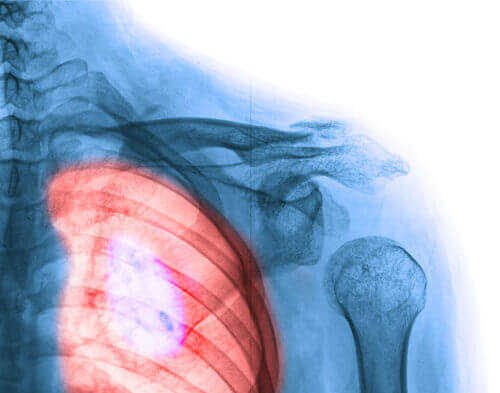

4. Longkanker

Dit is één van de meest voorkomende kankers bij vrouwen. In de laatste jaren komt het ook steeds vaker voor. Deze kanker heeft één van de hoogste mortaliteitscijfers bij zowel mannen als vrouwen.

In 80% van de gevallen ligt de oorzaak bij tabak. Roken, of je in ruimtes bevinden waar gerookt wordt, heeft ernstige gevolgen voor je gezondheid. Net zoals andere slechte gewoonten is dit dus zeker iets dat je moet vermijden als je geen ernstige ziektes wil oplopen.

Het aantal vrouwen dat rookt is de laatste jaren aanzienlijk toegenomen. Of er ontbreekt iets in de reclameboodschappen of de boodschap dringt gewoon niet door: Stop met roken voor je eigen gezondheid en gemoedsrust! Wees bedacht op volgende symptomen: